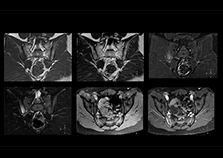

“On average, we scan about 80 patients per day, but on some days we scan well over 100 patients. The scanner is in use 7 days per week, operated 20 hours per day on week days and 8 hours per day in the weekend,” Mr. Tuna says. “To avoid coil changes we plan examinations of similar anatomies back to back, such as head and spine. Multiva helps us here a lot because coils don’t need to be changed frequently. Moreover, thanks to parallel imaging technology and 16-channel HeadSpineTorso and 8-channel MSK coils we are able to achieve excellent image quality. In this way Multiva helped us to increase both image quality and productivity.” “Neurological cases, such as brain and spine imaging, represent the largest share in our MR scanning, followed by musculoskeletal cases. In general, we use simple and basic imaging protocols. But occasionally, we use advanced techniques for problematic cases if necessary.

“Since we have Multiva, we have improved our workflow, because it has been so easy for our operators to learn and use Multiva. Our operators notice that the coils are lightweight and coils don’t need to be changed frequently. The user interface is easy to use. Features like this help us to scan a high number of patients. For instance, the musculoskeletal coils can be used interchangeably, and due to the user-friendly interface, the number of mistakes such as, for example, correct coil element selection has decreased significantly, because the system does it automatically by itself.” “Most important, Multiva satisfies our clinical imaging needs very well,” says Mr. Tuna. “Many features of Multiva have become similar to the Ingenia system. Even in more complex imaging such as abdominal and cardiac, the image quality and performance of Multiva is better than we expected. General surgeons and physicians from our hospital’s internal medicine department prefer to refer to us because of this.”

“Overall, Multiva provides what we need in term of patient needs and even potential needs,” says Mr. Tuna. “It allows us to scan a high patient volume and image a large variety of anatomies and conditions.” “Our goal is to achieve uncompromising quality based on universal standards, while solving clinically complex cases. Our Multiva scanner allows high productivity with fast imaging time, and allows us to make confident diagnoses in a broad range of cases.” “It’s an excellent multi-purpose scanner that satisfies all our MR imaging requirements in the hospital,” he concludes.